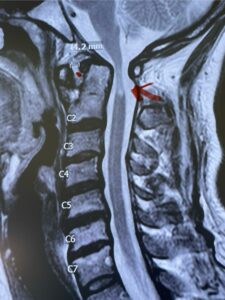

This is a 42 year-old female who presents with severe progressive weakness and numbness and difficulty with balance over a 6-month period. She has a history of having a motor vehicle accident at 5 years old but was never imaged. On exam she was noted to be severely myelopathic. Imaging revealed severe spinal cord compression at the level of C1 (Figs 4a and b).

Cervical x-rays revealed a significantly increased atlanto-axial interval (Fig. 5) On review of her imaging studies it was noted that the right C2 isthmus was very thinned by the vertebral foramen (Figs 6a, b, and c) which would make an attempt at placing a C2 pars screw dangerous. A decision was made to perform an occipital-cervical fusion because only possible unilateral fixation and an extensive C1 laminectomy to be performed eliminating a fixation point if a more traditional C1-C2 was performed. Even if C1 lateral mass screws were able to be placed one could only perform a unilateral screw construct fixation to C2. We performed an occipital cervical fusion down to C4 to get enough inferior fixation and C1 laminectomy. The decompression went well. We placed a left unilateral pars screw and bilateral C3 and C4 lateral mass screws. We placed three 12 mm screws in the midline keel (Fig. 7). Postoperatively the patient had all around improvement in her symptoms and did not qualify for rehab. Her post op films at 6 weeks (Fig. 8)

Fig. 6a: Sagittal cervical CT scan demonstrating an abnormally thin right C2 isthmus prohibiting safe placement of screw (red arrow). Notice the vertebral foramen eroding the isthmus bone structure (red dot).